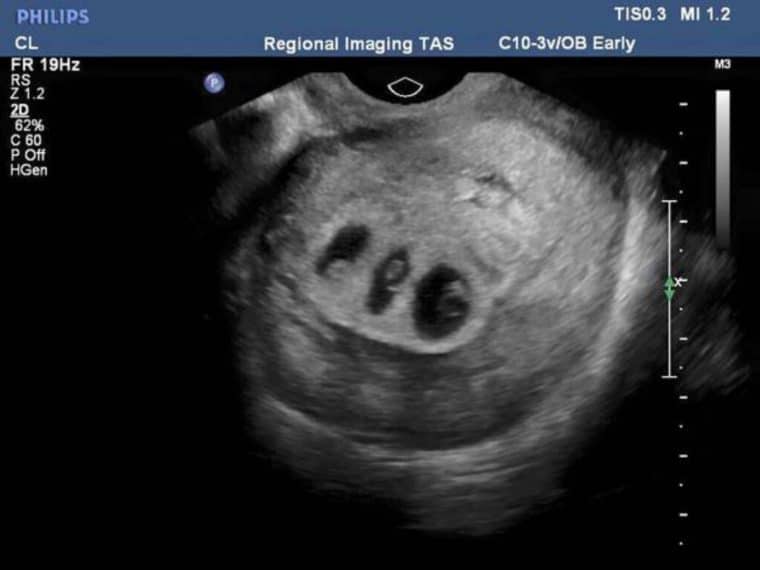

Na 28ª semana, ela fez um exame e descobriu: enquanto os dois meninos estavam bem, a garotinha parecia estar subdesenvolvida. A cada dia a situação ficava pior. Segundo os médicos, ela morreria a menos que fosse operada. A única questão é que isso poderia comprometer a vida dos outros dois meninos.